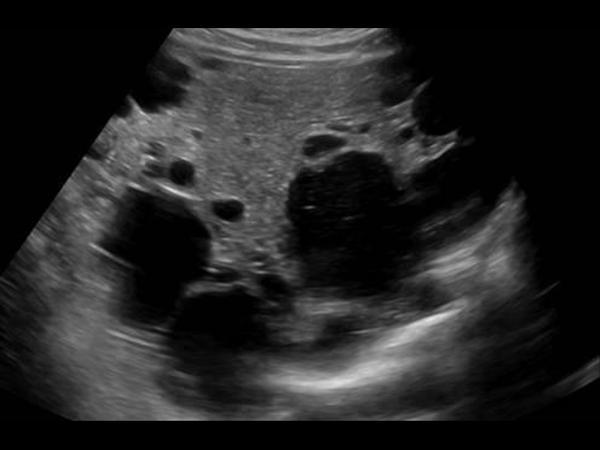

What is the sonographic appearance of Polycystic liver disease?

Anechoic

Thin well-defined walls

Posterior

enhancement

Multiple

Varying in small size